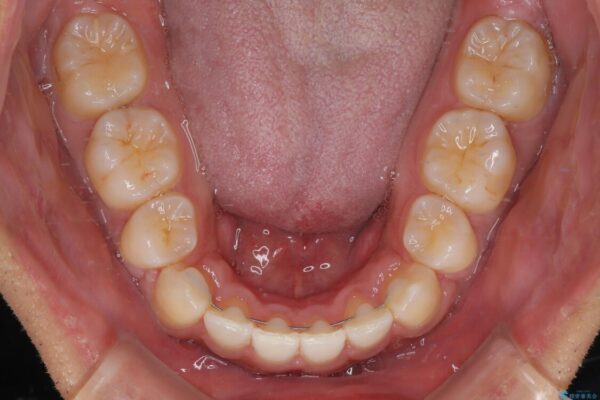

治療後

• 八重歯と前歯のガタガタを抜歯矯正で治療|クリアブラケット使用例 治療後画像

八重歯はきれいに整い、前歯もバランスよく収まり、横顔のラインも自然に改善されました。

そこで、上下左右の第一小臼歯を抜歯し、歯が並ぶためのスペースを確保し叢生を解消する治療計画を立てました。